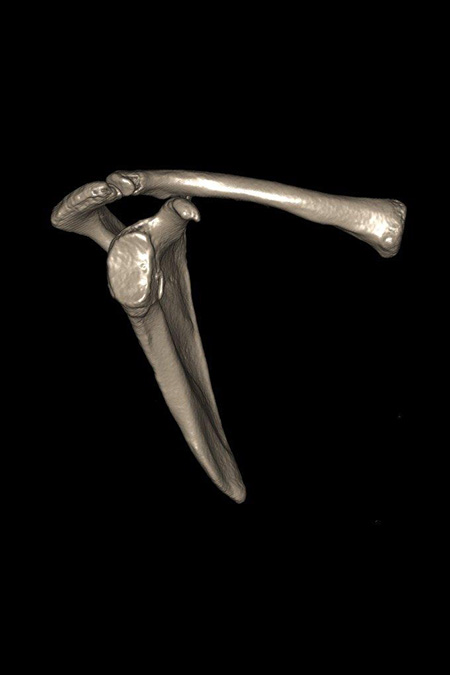

34 Jährige Patientin mit chronischer rechter Schulterinstabilität nach vorne unten. Bei der Analyse des Gelenkes fand sich in der 3D Schichtbilduntersuchung ein knöcherner Defekt (12% des Durchmessers) am vorderen unteren Pfannenrand. Operatives Vorgehen mit Spanaufbau des Defektes vom gleichseitigen Beckenkamm und Kapselstabilisation. Der Span wurde mit bioresorbierbaren Schrauben fixiert. Nach 3 Monaten bereits sehr gutes stabiles Bewegungsbild bei eingeheiltem Span. Noch Kraftaufbau erforderlich.

VORDERE CHRONISCHE SCHULTERINSTABILITÄT – KNÖCHERNER DEFEKT

Knöcherner Defekt am unteren Pfannenrand

Knöcherner Defekt durch Span ausgeglichen